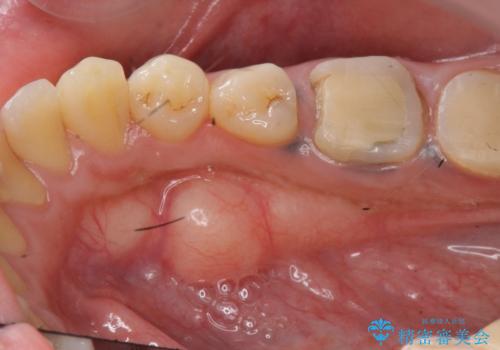

{ 歯周外科 } 骨隆起除去を含む歯冠長延長術

歯周外科を行うことで、歯ぐきの位置を下げ歯の高さを作り出し安定したクラウンの装着が可能となります。また同時に舌の邪魔となっていた骨隆起の除去を行うこととしました。